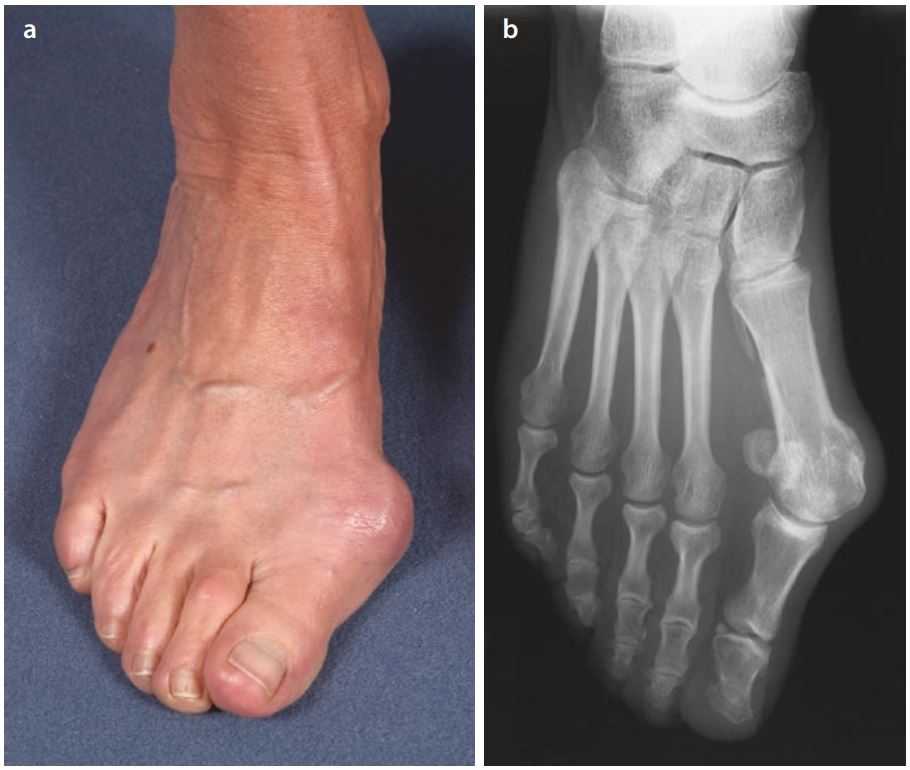

Der kritische Punkt für eine Operation der schiefen Großzehe – Hallux valgus

Die Schiefstellung der Großzehe ist eine häufige Veränderung. Die Frage ist oft, was noch toleriert werden kann und wann es angeraten ist, zu operieren. Probleme macht häufig der Ballen – die Vorwölbung des Mittelfußköpfchens, die Druck vom Schuh bekommt und gerötet ist.

Die ideale Fußform mit der regelrechten Wölbung an der Innenseite des Fusses und der Belastung des Vorfusses an den Randstrahlen, dem 1. Und 5. Mittelfußköpfchen, ist selten. Unsere Füsse haben wenig Freiraum, um die Schrittabwicklung ohne die Einwirkung des Schuhwerks zu machen. Sandalen bieten noch die größte Freiheit. Die meiste Zeit sind sie in festem Schuhwerk und wir trampeln auf ihnen herum. beginnt schon im Kindesalter.

Beschwerden treten in der Regel erst auf, wenn der Fuß ganz aus dem Gleichgewicht gekommen ist. Häufige Veränderungen finden an den Zehen statt. Die Kleinzehen können durch Schuhdruck und durch Muskelveränderungen mit Verlust der Balance der Muskel- und Sehnenzügeln an den Zehen zu Fehlstellungen als Krallen- oder Hammerzehen. Das kann sehr schmerzhaft sein, wenn durch Schuhdruck Hühneraugen entstehen und jede Berührung unangenehm ist. Polster zwischen den Zehen rauben zusätzlich Platz und verlagern nur die Probleme an einer Zehe auf die anderen. Oft geraten dadurch die anderen auch in eine Fehlstellung.

Die Grosszehe hat besondere Bedeutung bei der Abrollung des Fusses. Der letzte Druck beim Abstossen des Fusses kommt von der Großzehe. Wenn diese Abwicklung nicht mehr funktioniert, dann wird die Grosszehe oft noch mehr in die Schiefstellung gedrängt. Ganz wesentlich sind die Sehnenzüge an der Grosszehe. Sie halten die Grosszehe. Wenn sie verlagert werden, können sie die Grosszehe noch mehr in die Schiefstellung ziehen, wodurch die Kleinzehen auch verdrängt werden oder ich sogar übereinanderlegen.

Den kritischen Punkt, wann die Grosszehe rapide weiter in die Schiefstellung gerät und damit auch die anderen Zehen verdrängt, und deswegen gehandelt werden muss, kann jeder gut erkennen. Man sieht dies daran, dass sich die Grosszehe verdreht. Die verlagerten Sehnenzüge führen dann zu der schnellen weiteren Zunahme der Schiefstellung. Dann ist die Nagelplatte nicht mehr in der Ebene der Kleinzehen, sondern dreht sich mit der Zehe nach aussen (pronatorische Aufdrehung). Gleichzietig wird von der schiefen Grosszehe der Ballen noch weiter herausgedrückt. Bei einer solchen Verdrehung der Gorsszehe muss eine Operation erfolgen, um nicht noch weiter fortschreitende Veränderungen an den anderen Zehen und im ganzen Vorfuss zu riskieren.